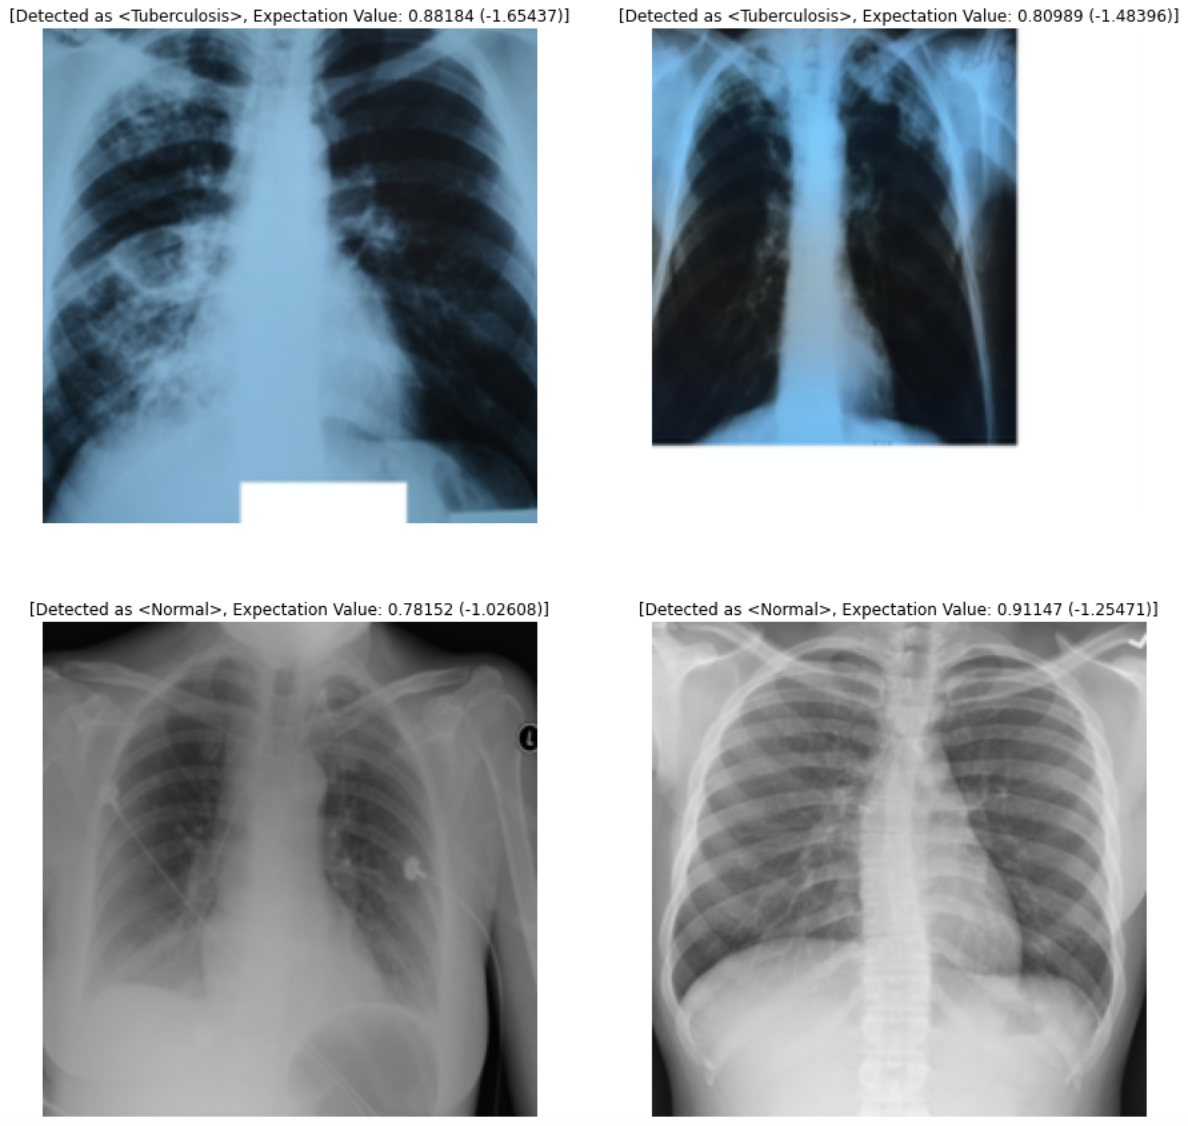

Results: Accuracy and Loss Score of Trained Model

The model reported a validation accuracy of approximately 92.5% and a loss score of approximately 20%, indicating the model was able to generalize and differentiate the categories correctly given the dataset images. Once the model is loaded in, it requires less than 2 seconds to make a prediction.